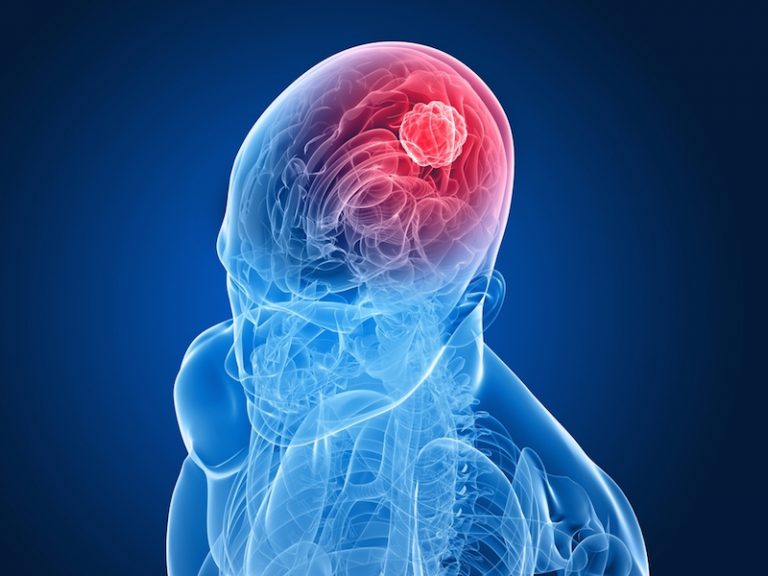

سرطان مغز از چالشهای جدی و پیچیده در دنیای پزشکی است که به دلیل رشد غیرطبیعی سلولها در مغز، میتواند تأثیرات گستردهای بر سلامت فرد داشته باشد. این نوع سرطان، که میتواند با علائمی چون سردردهای مزمن، تغییرات در وضعیت هوشیاری، تشنج و اختلالات حرکتی همراه باشد، یکی از...